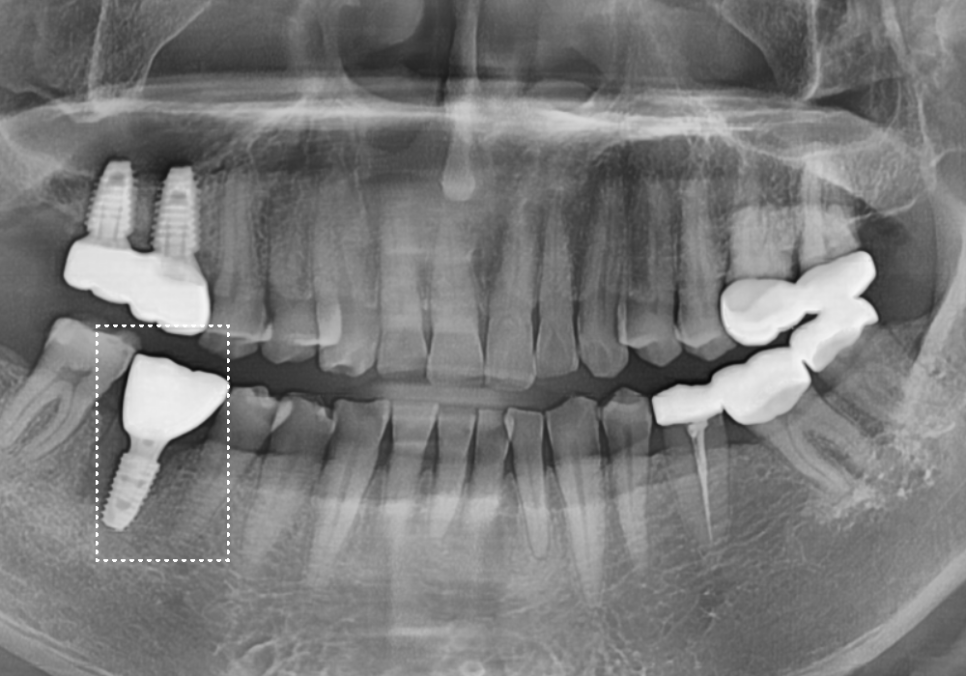

우선 발치 후 주변에 퍼진

염증을 깨끗하게 긁어내고,

부족한 뼈를 보강하기 위해 뼈이식과 함께

임플란트 뿌리를 정확한 위치에 식립해 드렸습니다.

식립 후 3개월 뒤,

뼈가 확실히 굳은 것을 확인하고

정밀 스캐너로 본을 떠서

최종 지르코니아 보철을 완성해 드렸습니다.